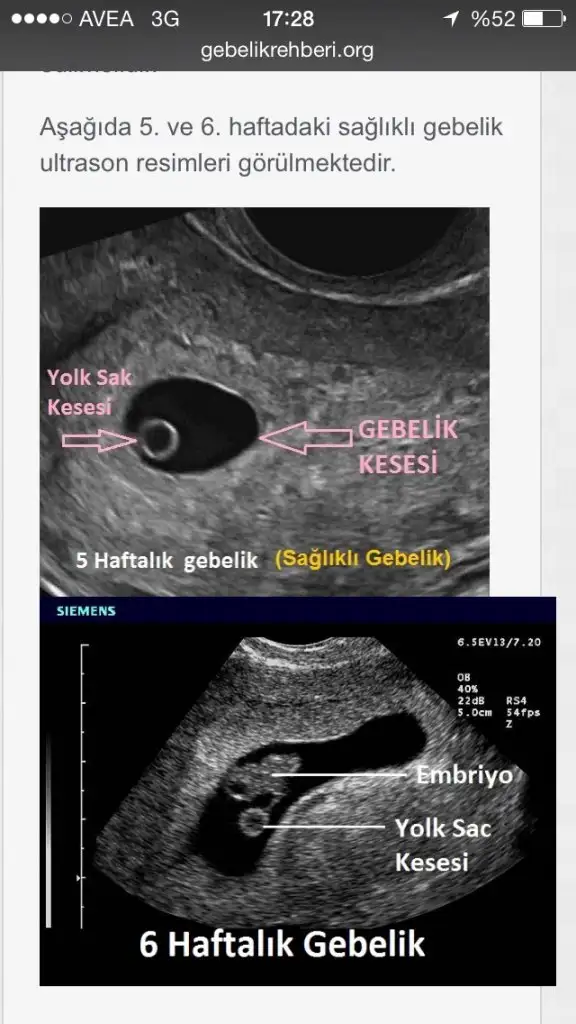

CNmboş gebelikte kese var ama için de embriyo yok zaten kalp atışı da olmuyor hcg artıyor ama yeterli değil üstteki boş gebelik alttaki sağlıklıboş gebelik nasıl oluyor canım ya...inşallah bir daha olmaz...geçmiş olsun..

SAĞDAKİ GİBİ SAĞLIKLI GEBELİKLERİMİZ OLSUNN İNŞA EN KISA ZAMANDACNmboş gebelikte kese var ama için de embriyo yok zaten kalp atışı da olmuyor hcg artıyor ama yeterli değil üstteki boş gebelik alttaki sağlıklı